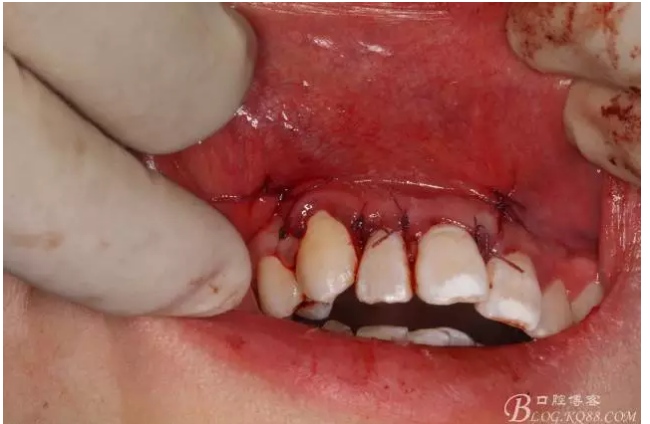

圖15.縫合垂直切口

圖16.縫合完畢,一周拆線。